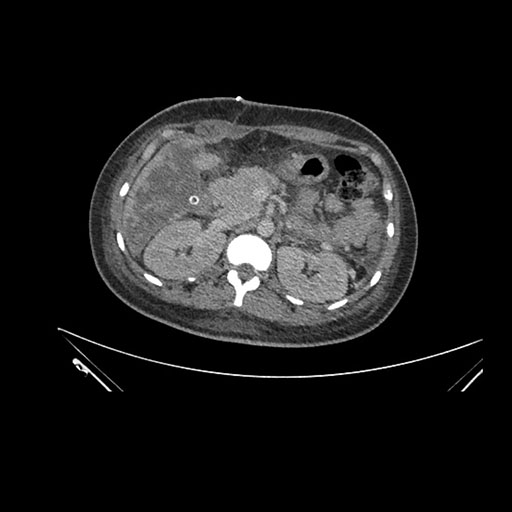

Axial Arterial

Imaging analysis

Based on initial findings, which issue(s) would you be most concerned about?